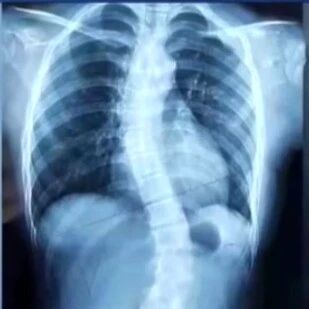

人体成分测定是评估肝硬化营养不良类型的一项重要方法。目前临床上多种检查手段可用于评估人体成分,如双能X线法、CT断层扫描法、磁共振法及生物电阻抗法等。其中,CT断层扫描法是测定骨骼肌、皮下脂肪及内脏脂肪组织的金标准[10]。CT扫描第三腰椎截断平面的骨骼肌面积代表全身骨骼肌质量是诊断少肌症的重要方法[5]。基于细胞液体重量与电阻抗值呈明显相关的原理,可用生物电阻抗法测得的电阻抗值,推算出细胞总液体量及细胞外液体量,从而分析人体成分。当输入电流低于50kHz时,电流不能通过细胞膜,此时只能测得细胞外液体量;当电流超过200kHz时,电流可以通过细胞膜,此时测得的水重量为总液体量。通过矫正体质量、性别、身高、年龄等,推算出肌肉、脂肪量等含量[11]。生物电阻抗法测定人体成分具有操作简便、安全、无创、无辐射、成本费用低廉等优点,但其结果容易受机体水肿影响,肝硬化患者多合并腹水,其检测结果评估应考虑这一因素。营养风险筛查工具(NRS2002)包括营养状态评分、疾病严重程度评分及年龄评分3个部分。欧洲肠外与肠内营养学会(ESPEN)指南建议所有肝硬化患者均需采用NRS2002进行营养风险评估,评分≥3,则存在营养风险[12]。由于少肌症是肝硬化患者预后不良的独立危险因素[13-14],在人体成分测定中,应重视少肌症的筛查。